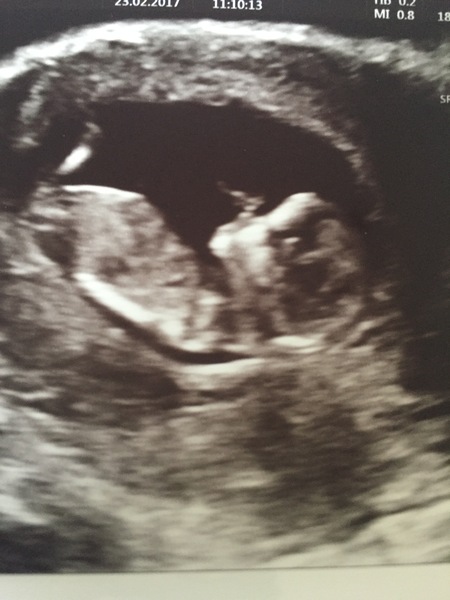

12w scan today - nuchal measurement perfect (phew - was a bit worried at my age) and so cool to see the baby! For it is indeed a baby now, stretching and swallowing and kicking and rubbing its face. DH reckons it looks like a boy (completely unscientifically). That would be cool! But another girl is lovely too

Have loads of scan pics but they're on a USB and I'm on my phone so I'll post later